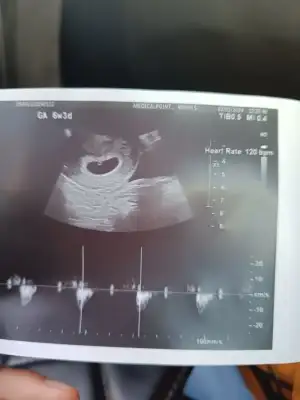

Bende kilo verdim hiçbir şey yiyip içemedim. Yani bebeğe yetecek kadar yedim ve gerçekten de öyle oldu bebeğin gelişimi bir hafta ilerde. Ama ben o kadar aç kalmışım ki vücut direncim çok düşmüş ve idrarda hem şeker hemde keton çıktı. Bu da açlıktan ve susuzluktan olmuş. Şimdi çok zorlanarak yiyorum ve tatlı yediğim zaman sabahlara kadar yatamıyorum çok rahatsızlanıyorum. Lütfen siz zorla da olsa yiyin. Kussanız da yiyin sağlıklı şeyler yiyin hep. İnanın bu zor günler geçicek. Benim şu an hastaneye yatıp sıvı almam lazım. Çünkü bebeğe geçerse büyük problem olur. Lütfen siz dikkat edin sizde de olmasın